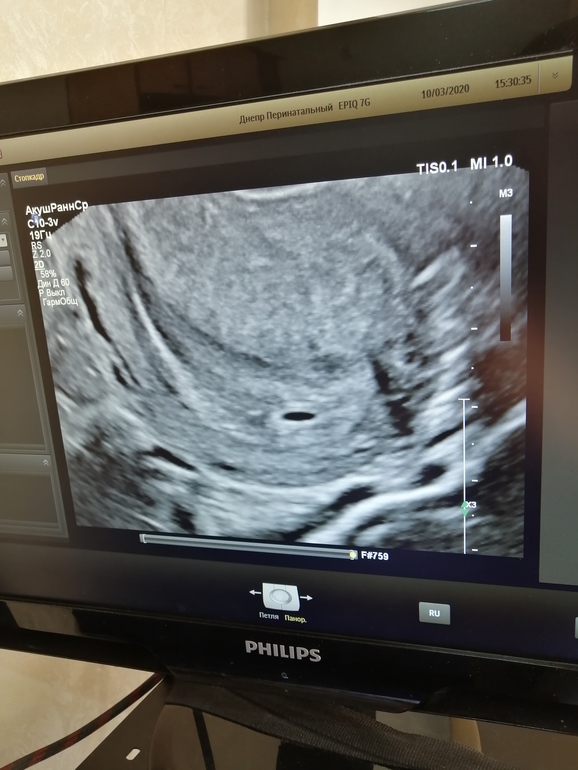

Наше первое УЗИ 🥺🥺🥺

Сказал, все хорошо, что все соответствует сроку. И сказал прийти на контроль через 2-3 недели, слушать сердце. Эмбриона ещё не видно и это нормально, срок то ещё маленький) Но я ХГЧ ни разу не сдавала, чтобы не переживать лишний раз

Поздравляю вас)) у меня сегодня 5 недель. Завтра иду на узи)) значит увидели на этом сроке)) я тоже очень надеюсь что маточная )) а у вас какие сейчас признаки ?) как самочувствие?) у меня чето особо и признаков нет, только есть хочется и вздутие и все

Все хорошо)) спасибо )) беременность маточная ))) через две недели ещё сказали прийти ))) у нас с вами почти одинаковый срок )) на 1 день только разница ))

Мне чето не сказали размер ПЯ. И заключения нет. Только написано что беременность 5 недель и все. Это я в платную ходила. Ничего не написали чето. Я и не спросила обрадовалась что маточная и все))